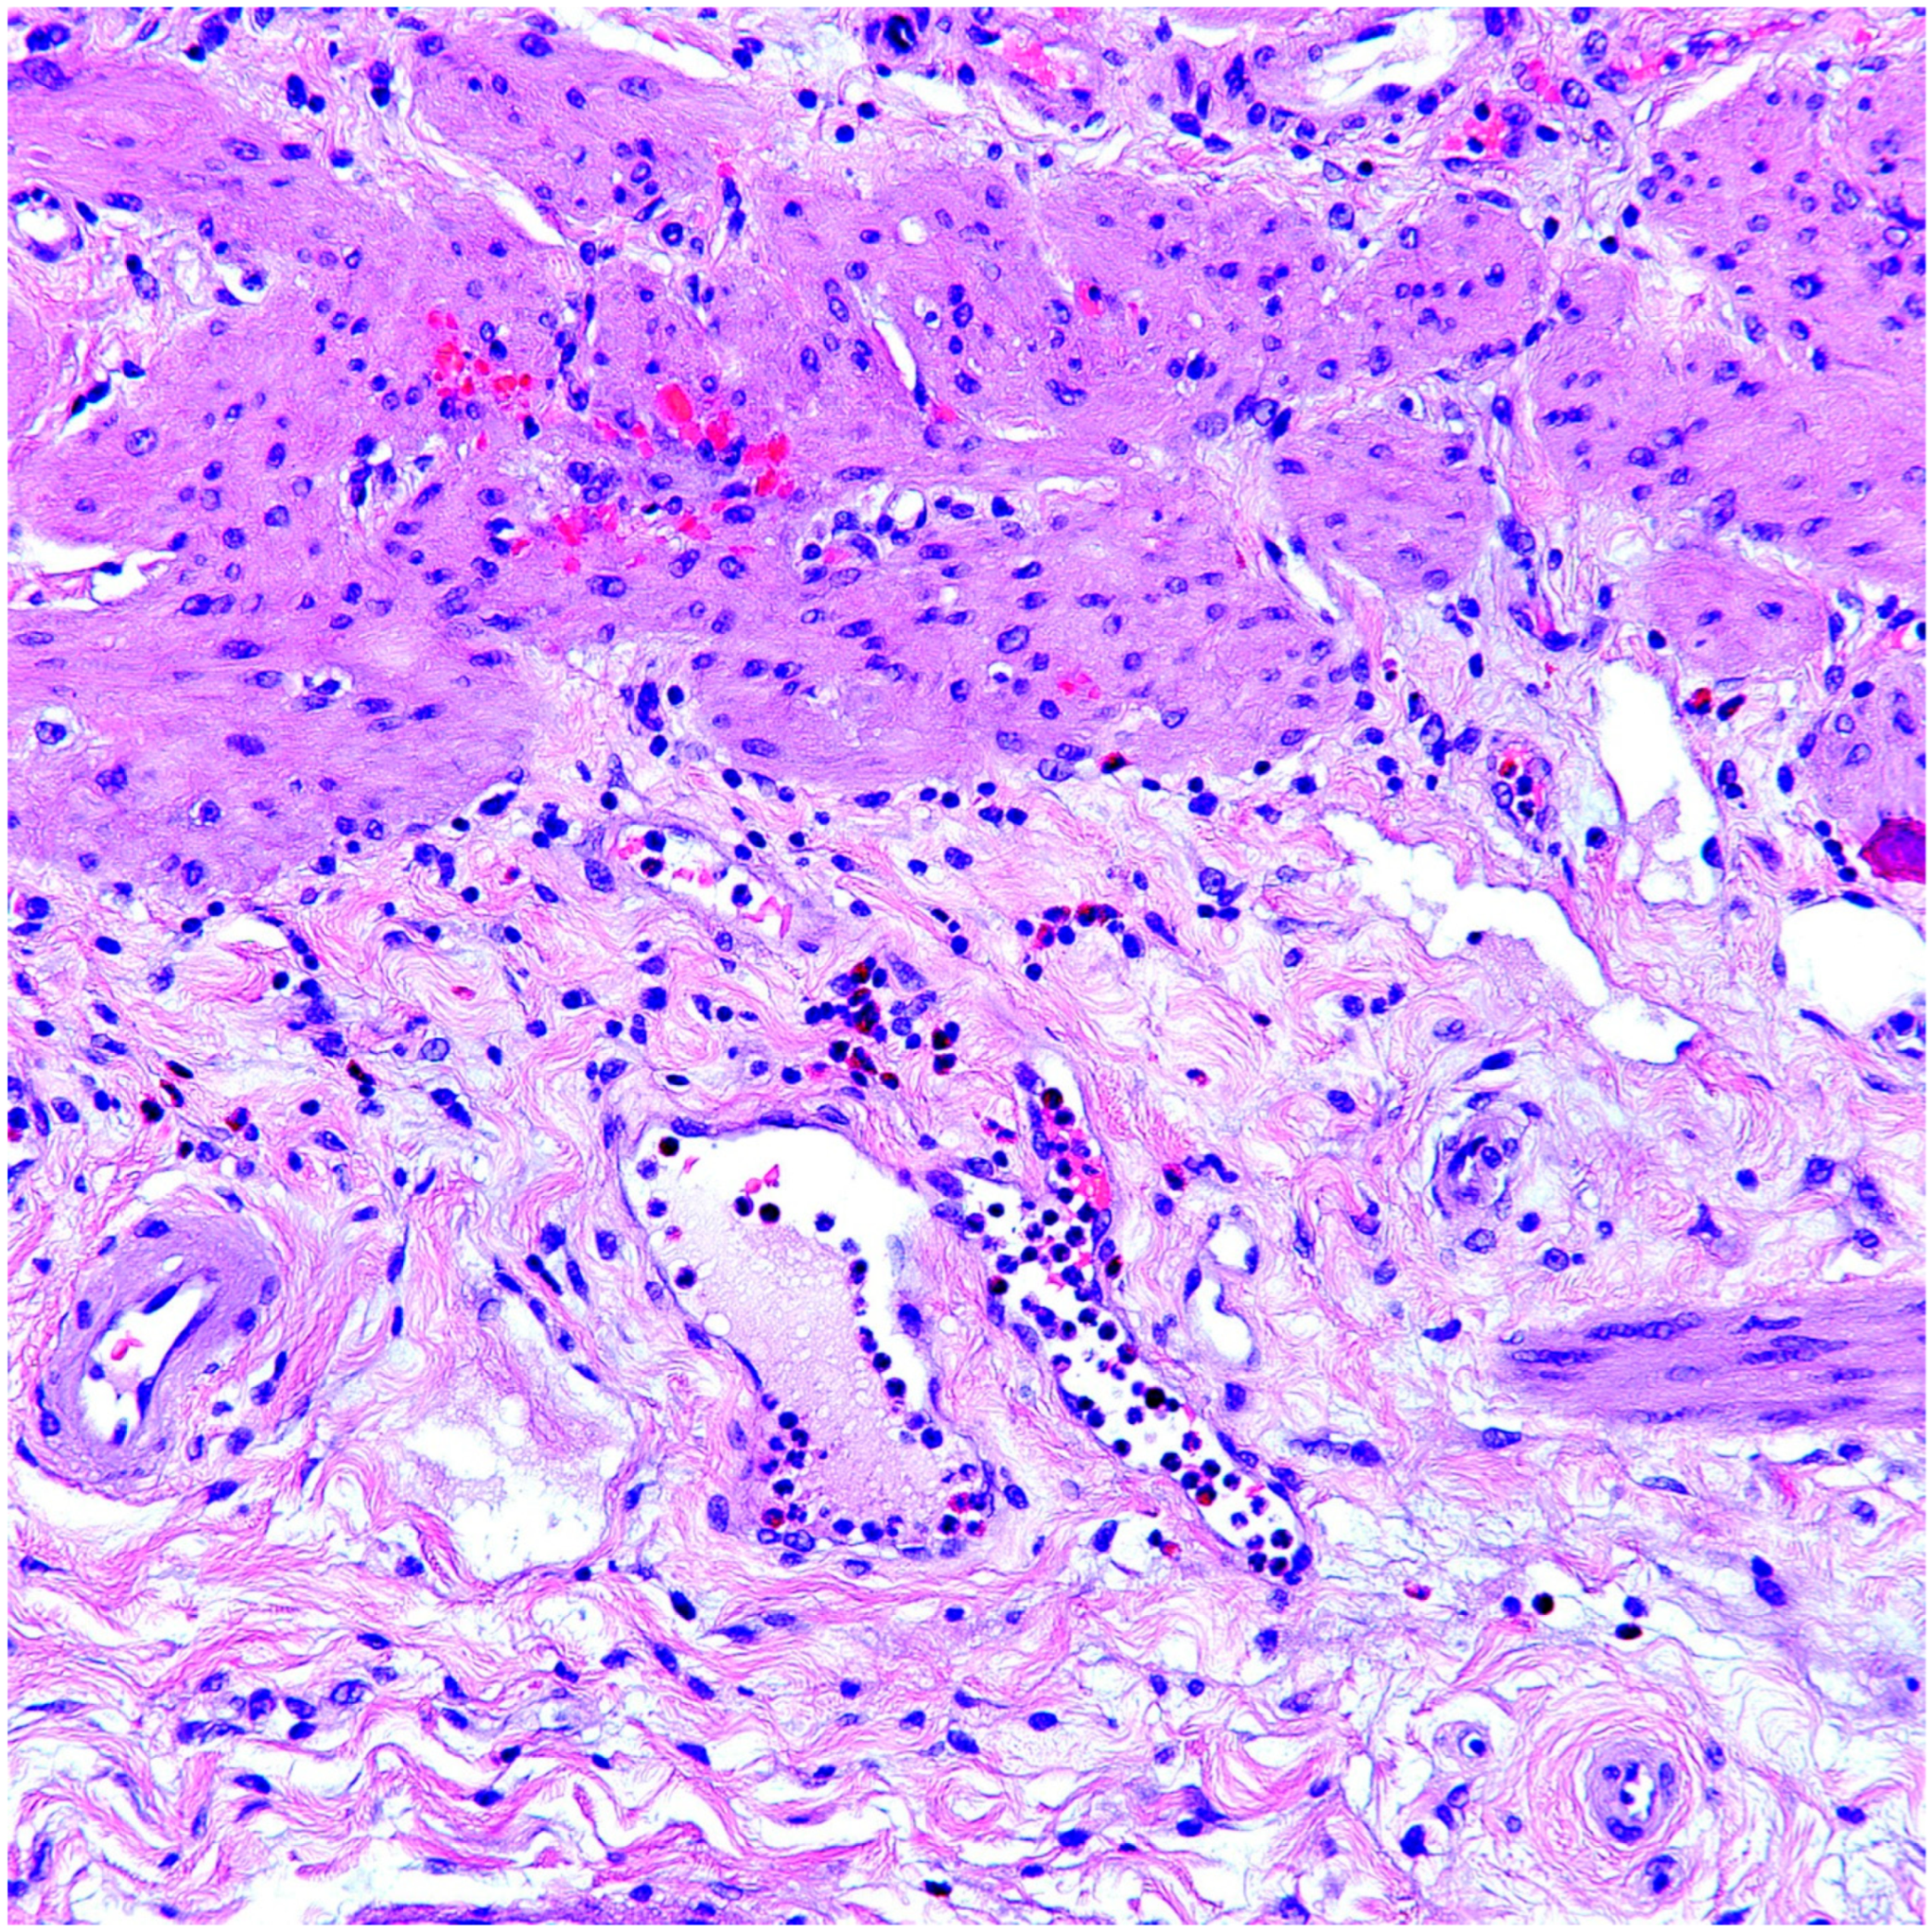

4. Discussion